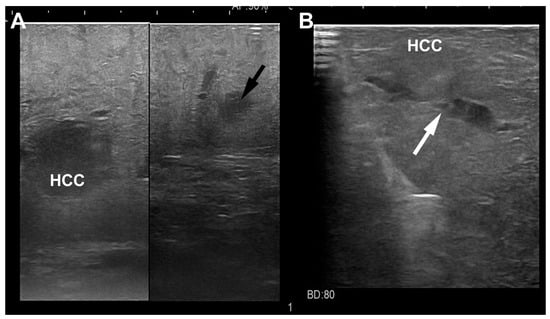

4. LUS Evaluation